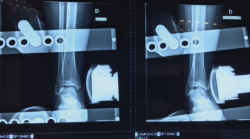

Figura 3. Radiografía en varo forzado. Tienen valor diagnóstico si son positivas. El varo forzado es positivo si existe un varo > 15° o una diferencia de > 10° respecto al tobillo contralateral.

- Varo forzado: positiva si existe un varo > 15° o una diferencia de > 10° respecto al tobillo contralateral (Figura 3).

- Cajón anterior: positiva si existe una traslación anterior > 1 cm o una diferencia > 3 mm respecto al tobillo contralateral (Figura 4).

Figura 4. Radiografía del cajón anterior. El cajón anterior es positivo si existe una traslación anterior > 1 cm o una diferencia > 3 mm respecto al tobillo contralateral.